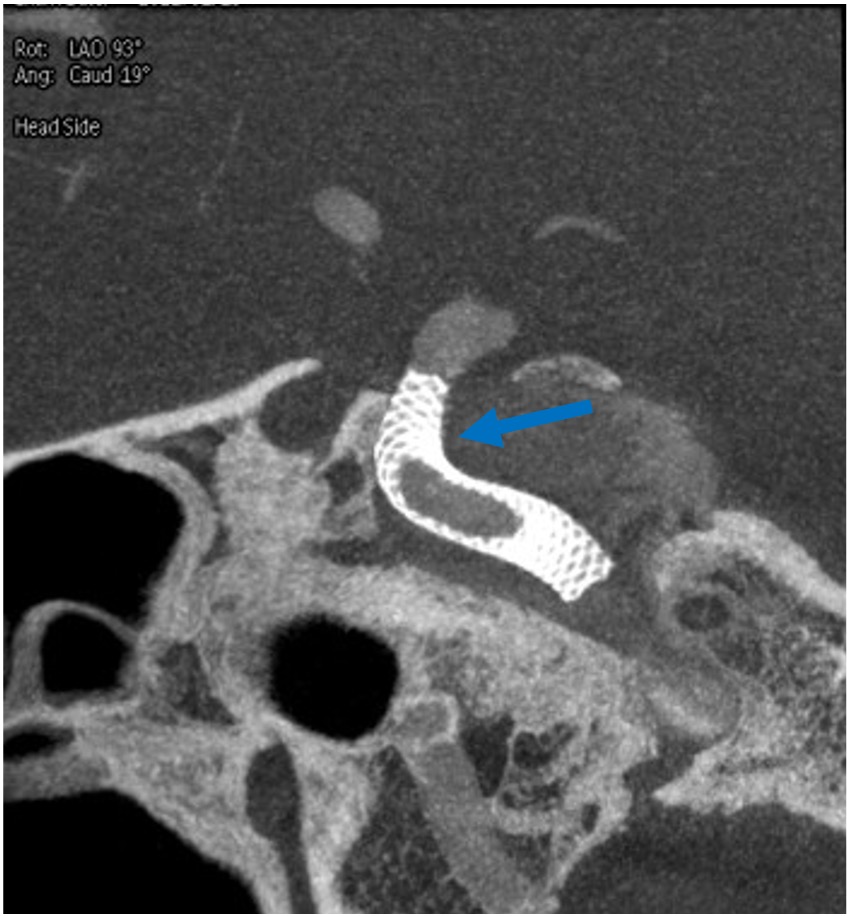

その1例を提示します。患者さんは65歳女性です。頭痛でMRIAを行い、血管撮影にて図1赤矢印の様に最大径7.8mm.ネック径4mmで、パイプラインというフローダイバーターステント(X線にて確認可能、図2〜5青矢印)を留置しました。その後、4ヶ月後の血管撮影ですが、図6緑矢印の様に動脈瘤は消失しています。